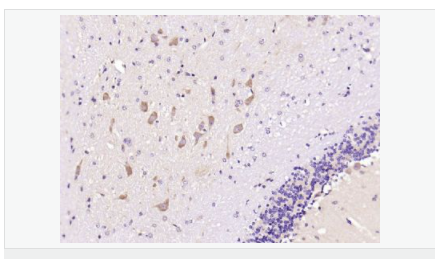

| 產(chǎn)品應(yīng)用 | ELISA=1:5000-10000 IHC-P=1:100-500 IHC-F=1:100-500 IF=1:200-800 (石蠟切片需做抗原修復(fù)) not yet tested in other applications. optimal dilutions/concentrations should be determined by the end user. |

| 產(chǎn)品介紹 | This gene encodes a member of the corticotropin-releasing factor family. The encoded preproprotein is proteolytically processed to generate the mature neuropeptide hormone. In response to stress, this hormone is secreted by the paraventricular nucleus (PVN) of the hypothalamus, binds to corticotropin releasing hormone receptors and stimulates the release of adrenocorticotropic hormone from the pituitary gland. Marked reduction in this protein has been observed in association with Alzheimer's disease. Autosomal recessive hypothalamic corticotropin deficiency has multiple and potentially fatal metabolic consequences including hypoglycemia and hepatitis. In addition to production in the hypothalamus, this protein is also synthesized in peripheral tissues, such as T lymphocytes, and is highly expressed in the placenta. In the placenta it is a marker that determines the length of gestation and the timing of parturition and delivery. A rapid increase in circulating levels of the hormone occurs at the onset of parturition, suggesting that, in addition to its metabolic functions, this protein may act as a trigger for parturition. [provided by RefSeq, Nov 2015] Function: This hormone from hypothalamus regulates the release of corticotropin from pituitary gland. Subunit: Interacts (via C-terminus) with CRFR1 (via N-terminal extracellular domain). Subcellular Location: Secreted. Similarity: Belongs to the sauvagine/corticotropin-releasing factor/urotensin I family. SWISS: P06850 Gene ID: 1392 Database links: Entrez Gene: 1392 Human Entrez Gene: 12918 Mouse Omim: 122560 Human SwissProt: P06850 Human SwissProt: Q8CIT0 Mouse Unigene: 75294 Human Unigene: 290689 Mouse Unigene: 10349 Rat Important Note: This product as supplied is intended for research use only, not for use in human, therapeutic or diagnostic applications. CRF陽性神經(jīng)元的胞體廣泛分布于下丘腦的室旁核、背縫核和藍斑核,這些區(qū)域也是去甲腎上腺素(NE)神經(jīng)元與5-羥色胺(5-HT)神經(jīng)元密集的區(qū)域。 CRF既具有神經(jīng)遞質(zhì)的性質(zhì)又具有神經(jīng)激素的性質(zhì)。CRF是聯(lián)系神經(jīng)系統(tǒng)與內(nèi)分泌系統(tǒng)的橋梁,在情感障礙疾患如焦慮和抑郁的發(fā)病中發(fā)揮重要作用. |